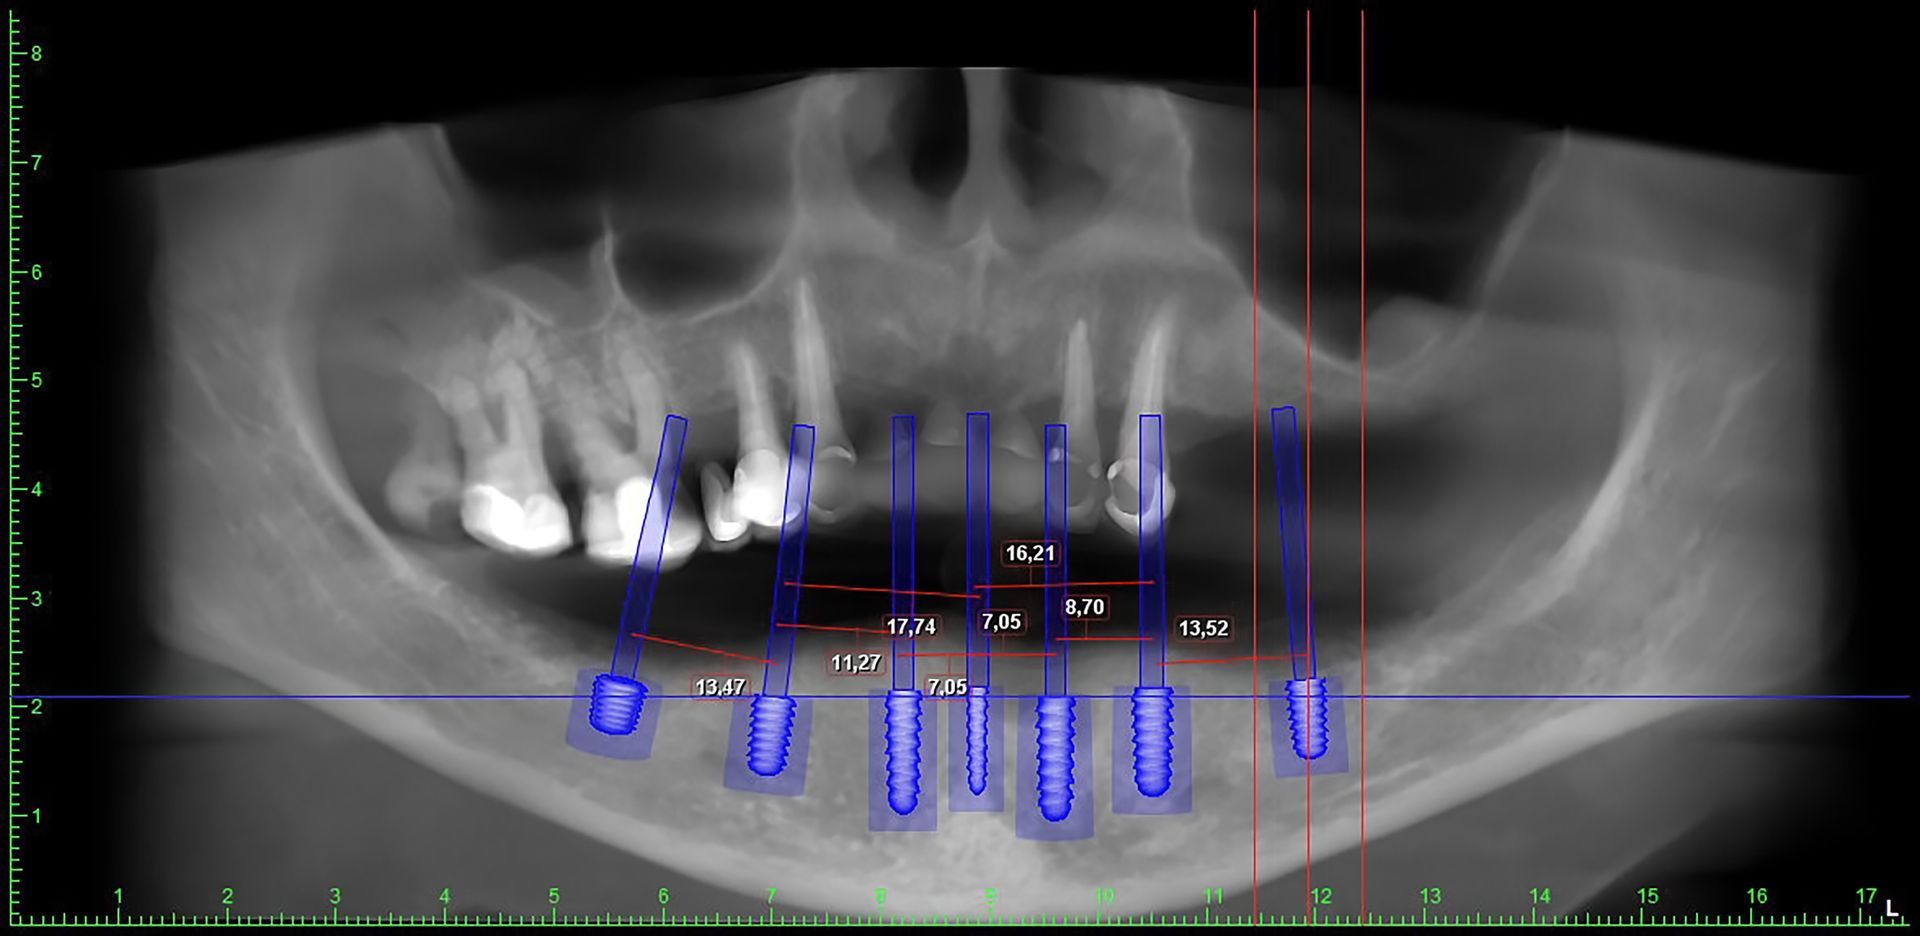

- implantologico o pre-implantologico;

- implantologia, nel momento in cui bisogna predisporre i tessuti di sostegno, prima dell’applicazione di un impianto;